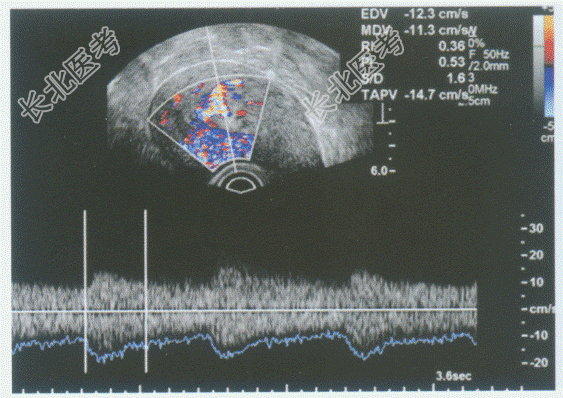

- 单项选择题临床资料:女性患者, 22岁,自述月经量增多淋漓不止。超声综合描述: 经阴道扫查子宫前位,形态大小正常, 肌层回声均匀,宫腔内可见1.7cm×0.7cm中等回声区(+…+所指), 宫腔线连续中断,CDFI: 可见彩色血流自蒂部伸入其内。见下图及彩图。超声提示: